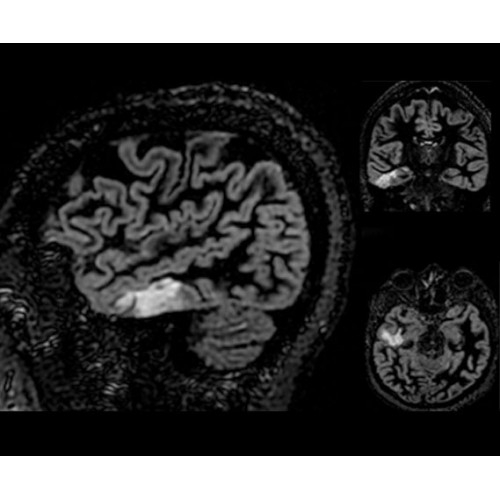

В системе SIGNA PET/MR есть все инструменты, необходимые для выявления маркеров разных заболеваний и для создания новых протоколов. ПЭТ/МРТ можно использовать совместно с мультиядерной спектроскопией в лаборатории in vivo для изучения быстрых биохимических процессов. Кроме того, PET ToolBox и набор инструментов Orchestra предоставляют персональный доступ к функциям реконструкции изображений для ПЭТ и МРТ, ускоряя и упрощая работу с необработанными данными.

• Специальный пакет приложений для измерения и сравнения объемных изображений ЦНС с нормами поможет вам в диагностике нейродегенеративных заболеваний, а дополнительные инструменты визуализации — в постановке точного диагноза с помощью бета-амилоидов и радиоизотопных маркеров ФДГ.

• In vivo лаборатория — получайте полные данные биохимических процессов in vivo с мультиядерной спектроскопией на SIGNA PET/MR.